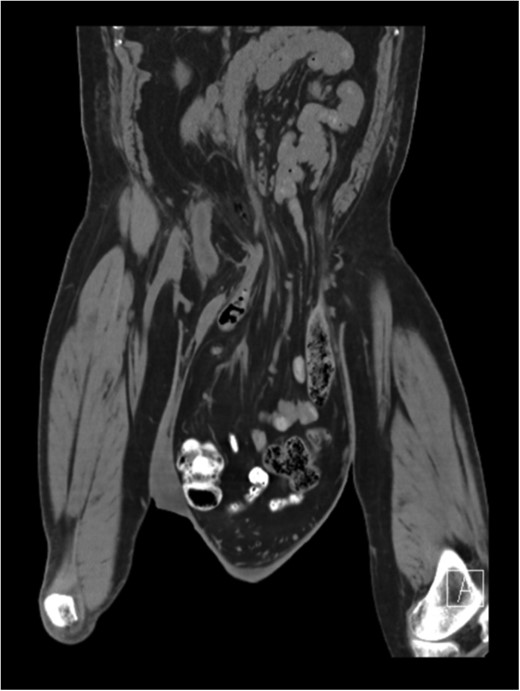

Pulmonary function test revealed no abnormalities. Electrocardiogram was normal, however, an echocardiogram confirmed systolic congestive heart failure with an ejection fraction of 30%. Patient preoperatively underwent a rigorous respiratory exercise and cardiac evaluation. Pre-operative computed tomography (CT) scan showed omentum, small and large bowel within the left scrotum Figs 2 and 3. Consent for the procedure was obtained including orchiectomy, bowel resection. Patient was mechanically bowel prepared the night prior to surgical intervention.

CT Scan showing small and large bowel within left scrotal sac.